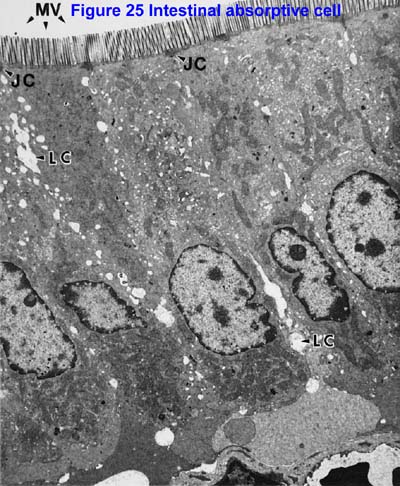

Electron Micrographs mitosis cell diagram labeling